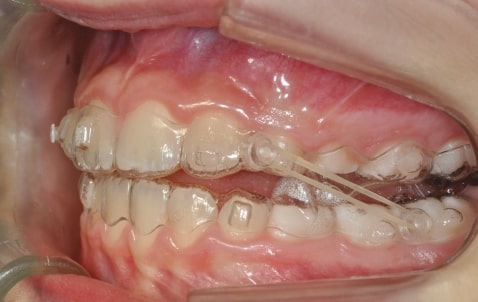

Malocclusion A6 Correction of Mandibular Retrusion in Growth phase patient | Skeletal Class II | Class II Division 1 malocclusion | Deep bite | Mixed dentition

Initial Photos and datas

Clinical examination and diagnosis

DENTAL:

• Molar and Canine class 2 on the right side – Molar and Canine clss 1 on the left side

• Upper diastema (11-21)

• Increased Overjet

• DeepBite

• Reduced Transversal Diameters

• Deviated Lower Midline 2 mm to the Right